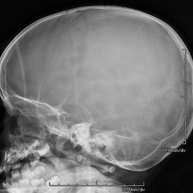

- RX Cráneo

Técnica mediante la cual, utilizando rayos X, se obtienen imágenes del cráneo para su estudio. Indicaciones: traumatismo, cierre precoz de suturas craneales. - RX Senos Paranasales